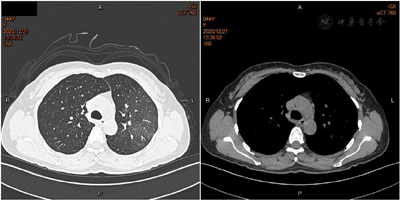

入院后予头孢他啶2 g 1次/12 h静点抗感染治疗,患者仍持续高热且出现干咳,体温最高40.2℃,予赖氨匹林、吲哚美辛栓退热后体温仍未下降至正常范围,2 d后复查降钙素原升高至0.059 ng/ml,考虑感染未能控制,常规实验室检查致病菌不明,经患者同意并签字,行支气管镜检查,肺泡灌洗液送检mNGS查找致病菌。治疗上考虑覆盖菌群不完全,不典型菌感染、病毒感染不除外,抗感染治疗方案调整为莫西沙星联合亚胺培南、奥司他韦。中药治以辛凉解表、宣肺泄热为主,方以麻杏石甘汤合银翘散加减(麻黄9g,杏仁9g,石膏10 g,炙甘草10 g,葛根10 g,知母10 g,浙贝母10 g,瓜蒌10 g,黄芩9 g,金银花10 g,连翘10 g,生姜6 g,大枣10 g),当晚患者体温下降至正常范围。3 d后患者出现咳嗽伴少量黄痰,略有胸闷,口干不欲饮,双下肢皮肤可见红色斑点,皮温高,无凸起,无瘙痒、疼痛,舌暗红,苔白腻,脉细。复查血常规出现白细胞、中性粒细胞下降,WBC 2.82×109/L,Neu 1.24×109/L,PLT 311×109/L,CRP 59.3 mg/L,肺泡灌洗液mNGS回报检出鹦鹉热衣原体(序列数33),追问病史,患者发热前家中曾喂养过4 d鸽子,综合考虑鹦鹉热衣原体感染,治疗首选四环素类,而四环素耐药率高,大环内酯类、喹诺酮类亦有效,停用亚胺培南,改为阿奇霉素。中药治以清营解毒、化痰散结为主,方用清营汤合小陷胸汤(水牛角9 g,生地15 g,麦冬15 g,玄参15 g,金银花15 g,连翘15 g,竹叶10 g,丹参15 g,黄连6 g,瓜蒌15 g,清半夏6 g)。3 d后复查血常规示白细胞、中性粒细胞升至正常范围,CRP降至12 g/L,胸部CT提示感染灶较前范围明显增大,密度明显减低(图3),考虑感染整体较前减轻,患者自觉咳嗽、胸闷、口干等症状较前减轻,双下肢斑点较前变淡,皮温正常,中药效不更方,原方加党参10 g益气生津。患者已一周无发热,双下肢皮肤红色斑点变浅,于2020年12月23日出院,出院带药盐酸莫西沙星片(0.40 g 1次/d)、阿奇霉素片(0.50 g 1次/d)、中药口服一周。

后患者未再发热,出现咳嗽伴少量黄痰,略有胸闷,口干不欲饮,双下肢皮肤可见红色斑点、皮温高。考虑风温表证不解而肺热渐炽,热郁于肺,炼液为痰,痰热结聚于胸部,2次胸部CT影像变化提示肺部病灶进展可能,故见咳嗽黄痰、胸闷;"热闭营中,故多成斑疹",为气分热邪深入营分,营血热甚而迫血妄行,血从肌肉外渍而见斑点;营热蒸腾则口干不欲饮;舌脉较前无明显变化,据症舌脉,辨证为痰热壅肺证,符合温病易内陷生变、化燥伤阴的特点。中药治以清营解毒、化痰散结为主,方用清营汤合小陷胸汤。方中以水牛角为君药,性苦寒,可清解营分热毒。生地凉血养阴,麦冬清热养阴生津,玄参滋阴降火解毒,三药皆甘寒质润,既养阴生津,又助君药清营热、凉血解毒,为臣药。金银花、连翘、竹叶清热解毒、透热毒邪气外达,即叶天士"入营犹可透热转气"之意,丹参苦寒清热凉血,活血祛瘀,可防热与血结,深陷血分,黄连、瓜蒌、清半夏清热涤痰、宽胸散结,共为佐药。患者服药后症状改善,双下肢皮肤红色斑点变浅,复查CT肺部炎症逐渐吸收,但余邪尚未完全清除,津液尚未恢复,原方加用党参益气生津至恢复正常,正符合叶天士所言"斑疹皆是邪气外露之象",斑疹顺利透发,邪热外泄,病情渐趋好转。既往病例报告也提示鹦鹉热感染后期存在气阴不足之象,先予黄连解毒汤加味治疗热毒壅盛证,继之予生脉散益气养阴[10]。相关研究也表明中医药参与治疗肺炎临床效果良好。广东地区在温病学理论指导下研制"肺炎1号方"治疗新冠肺炎患者症状改善明显[11];清金化痰方联合西医治疗社区获得性肺炎有效率是常规西医治疗的1.14倍,且缩短了临床症状体征持续时间,改善了炎症指标[12];麻杏石甘汤联合阿奇霉素治疗小儿支原体肺炎疗效显著、安全性好[13]。